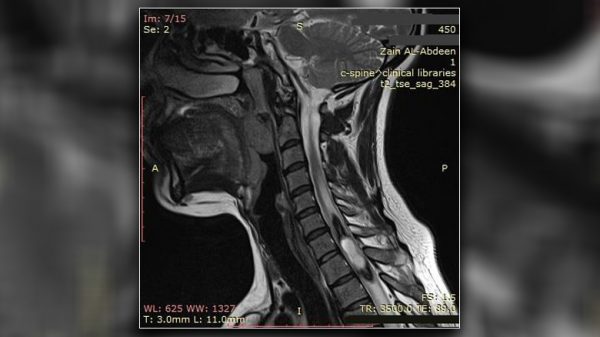

الحكمة – متابعة: أعلن مستشفى الإمام زين العابدين عليه السلام التابع للعتبة الحسينية المقدسة نجاح فريق الجراحة العصبية بإجراء عملية جراحية لرفع ورم من النخاع الشوكي لمريضة تعاني من “ألم رضي”.

وأفاد إعلام المستشفى ان المريضة راجعت المستشفى وهي تعاني من “ألم رضي” مع ضعف وتشنج الأطراف العلوية والسفلية, وعم القدرة على المشي.

وأضاف بعد إجراء الفحوصات لها تبين وجود ورم ضمن النخاع الشوكي, واجريت لها العملية وتم رفع الورم عبر مدخل خلفي في النخاع الشوكي باستخدام المجهر الالكتروني.

وأوضح إعلام المستشفى ان المريضة خرجت من العملية الجراحية بصحة جيدة, وتم تحويلها الى العلاج الفيزيائي، مشيرا الى ان نتائج تحليل عينة الورم أثبتت انه من نوع (Ependymoma) الذي يعرف بـ “ورم البطانة العصبية”.